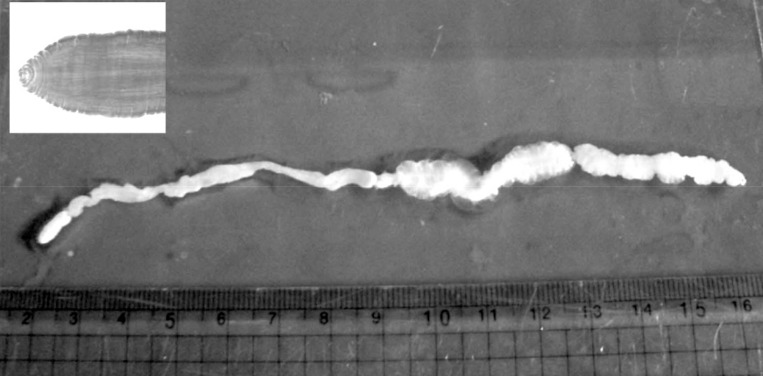

During the surgery, a longitudinal incision was made on the lateral aspect of the right lower leg. A soft, movable, and poorly marginated mass with a diameter of 2 cm was observed. The same as the previous operation, a white-shiny, synovium-like piece of body popped out through the incision, and determined as a sparganum. The removed worm was 15 cm in length, slightly shorter than that of the previously removed one (18 cm in length), and the scolex was easily seen (Fig. 2). After removing the sparganum, neuroraphy was performed because a ruptured sural nerve was observed. The pathological examination revealed chronic granulomatous inflammation with a degenerating parasite caused by a parasitic (possibly sparganum) infection. The patient's symptoms were improved thereafter and considered not reappeared again for more than 2 years after the second operation.